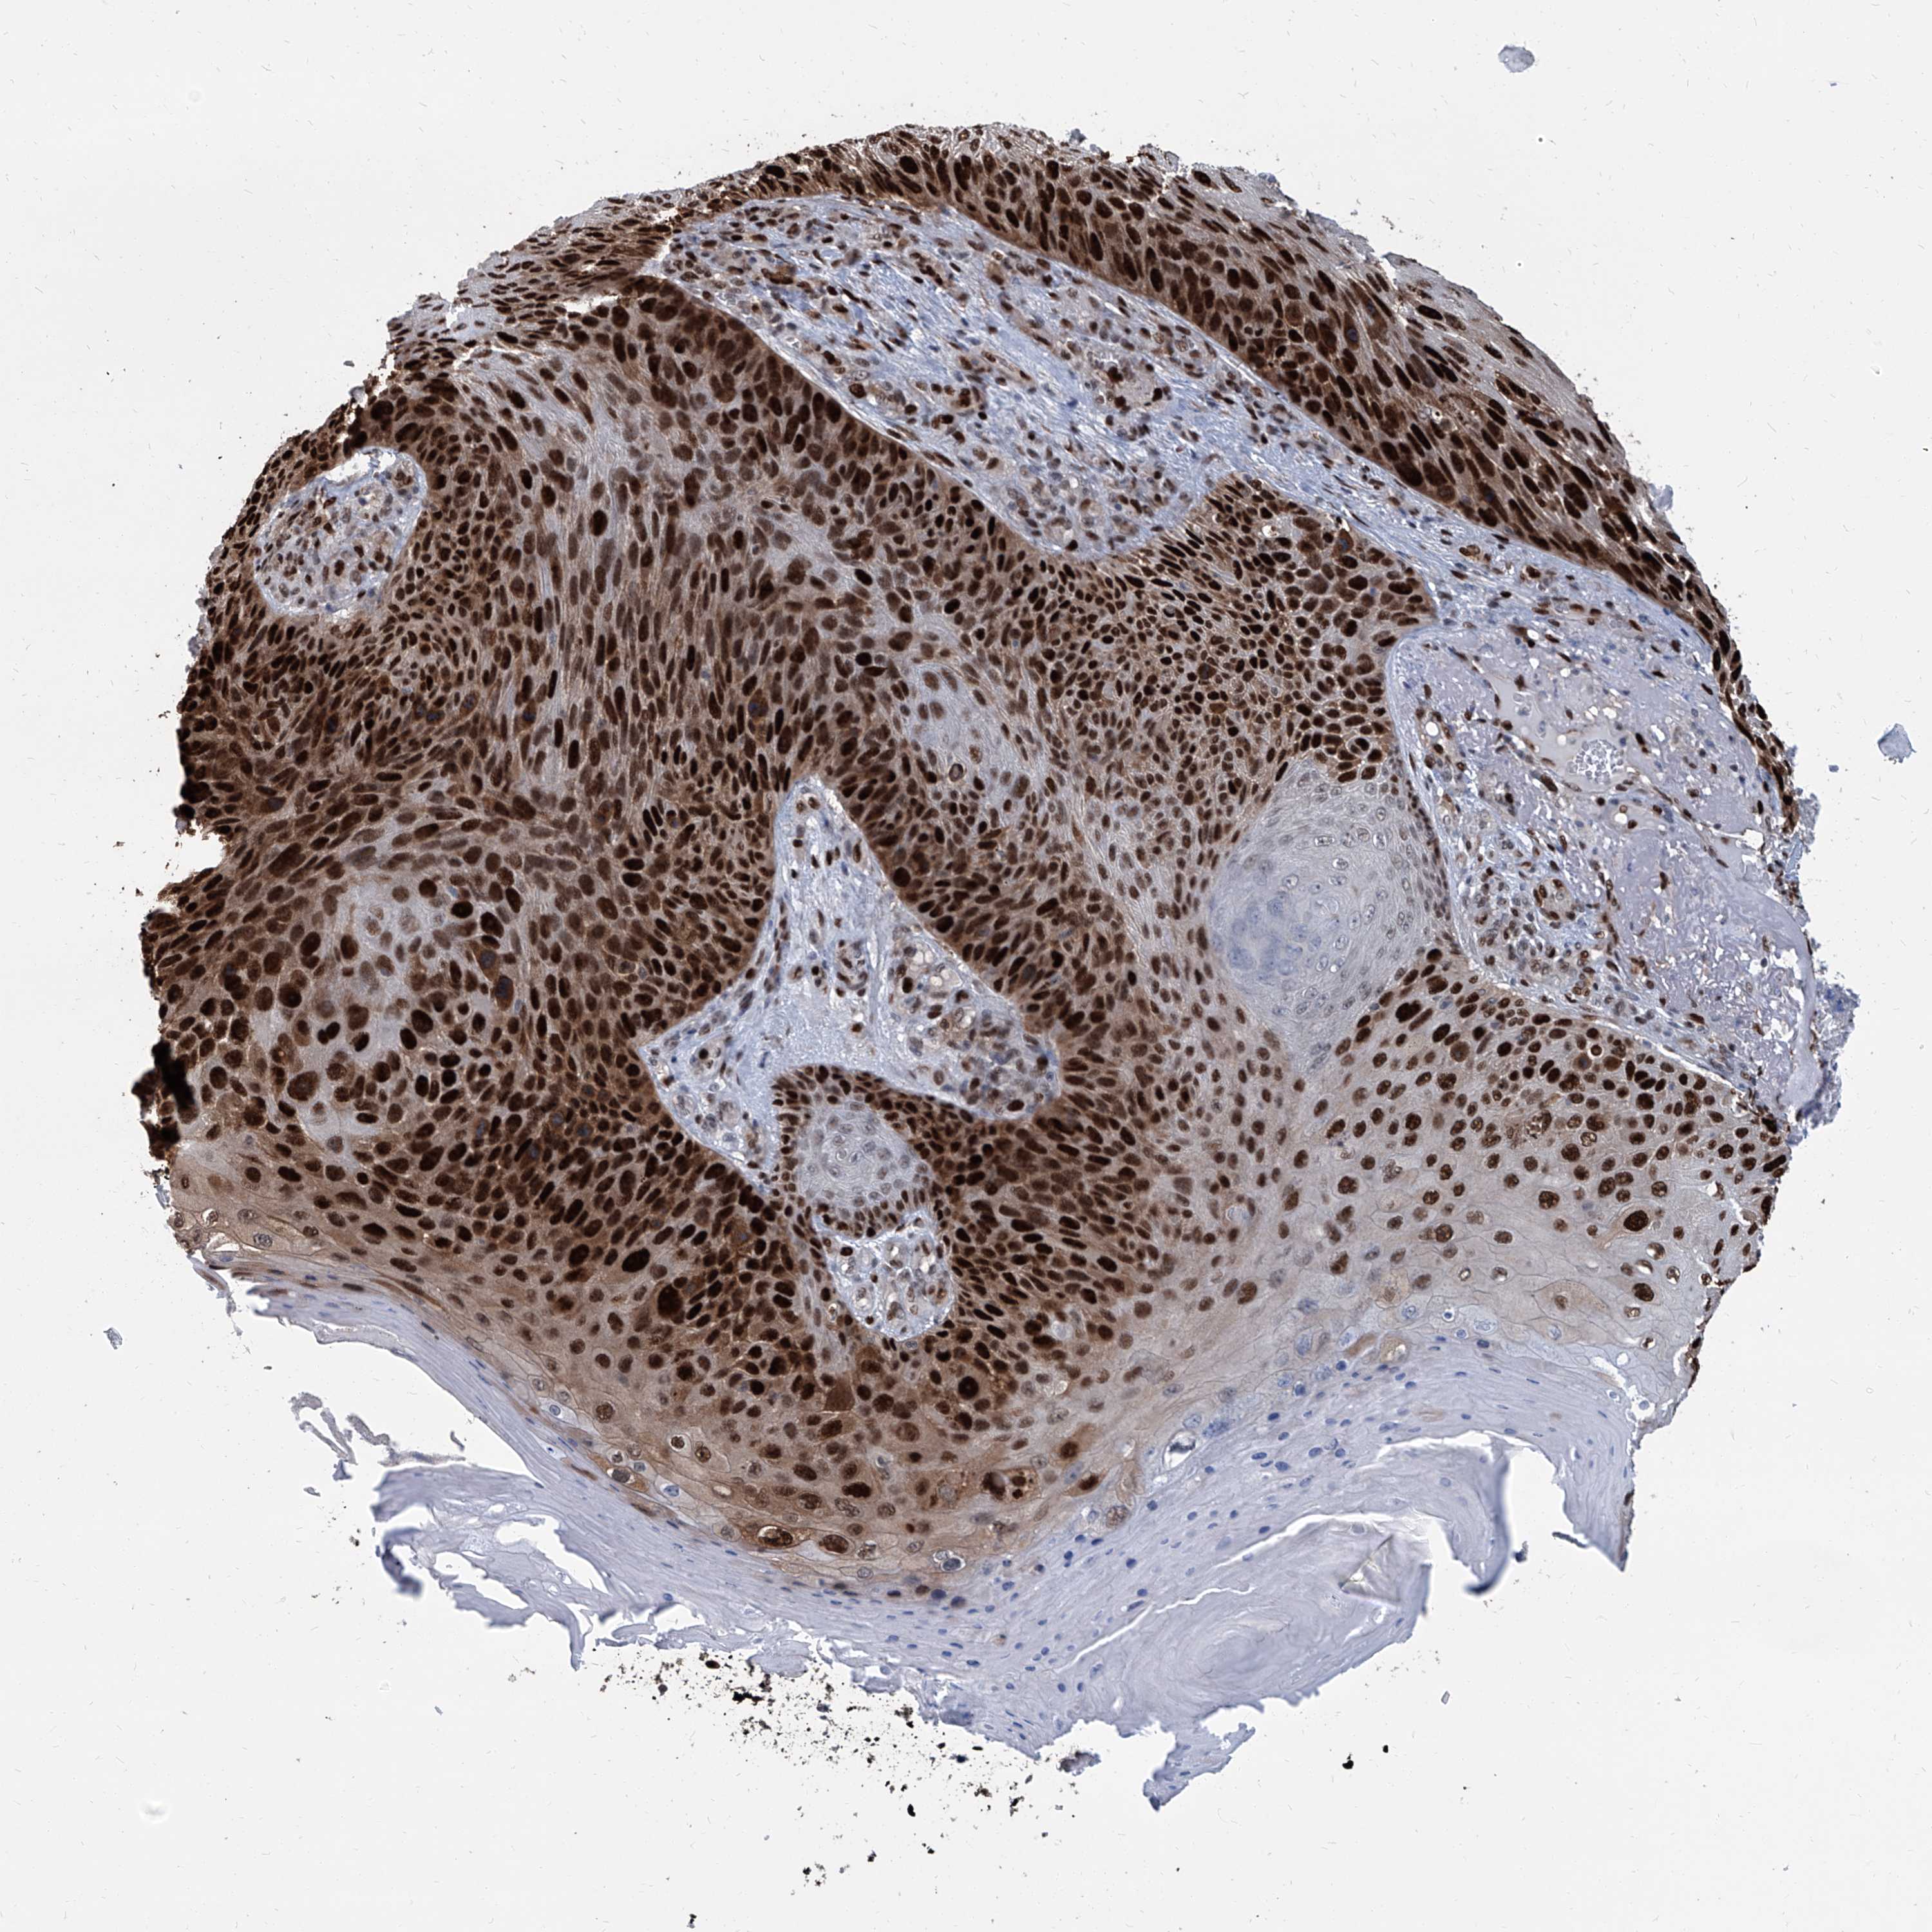

SKIN CANCER - Protein expressioni

A mouse-over function shows sample information and annotation data. Click on an image to view it in a full screen mode. Samples can be filtered based on level of antibody staining by selecting one or several of the following categories: high, medium, low and not detected. The assay and annotation is described here.

Each image is clickable and will lead to virtual microscopy that enables deeper exploration of all samples and also displays staining intensity scores, fraction scores and subcellular localization as well as patient and tissue information for each sample.

HPA030521

HPA030522

HPA030523

CAB000148

CAB080240

CAB080241

CAB080242

Staining

High

Medium

Low

Not detected

Intensity

Strong

Moderate

Weak

Negative

Quantity

>75%

75%-25%

<25%

None

Location

Nuclear

Cytoplasmic/membranous

Cytoplasmic/membranous,nuclear

Basal cell carcinoma

Squamous cell carcinoma, NOS

Squamous cell carcinoma, metastatic, NOS